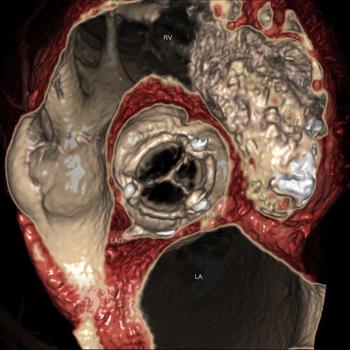

In the battle against patient overdose, Toshiba America Medical Systems brought two weapons to RSNA 2010. One is its Adaptive Iterative Dose Reduction (AIDR), software similar in approach to products from competing CT vendors who use iterative reconstruction to squeeze noise out of their images. The other, Target CTA, is a dose protocol devised specifically for cardiac scans done on the Aquilion One.